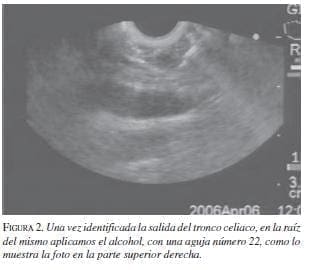

Los primeros en describir la técnica fueron Wierseman y colaboradores (11). La localización de los ganglios celiacos en la raíz del tronco celiaco es fácil por ecoendoscopia debido a la proximidad de éste con la pared gástrica (figura 1). Una vez se ubica el tronco celiaco, se puede utilizar una técnica central en la cual se aplican 20 ml de alcohol al 98% (figura 2) o una técnica bilateral en la cual se aplican 10 ml a lado y lado del tronco celiaco. Las dos técnicas tienen una eficacia similar; nosotros preferimos la primera debido a su facilidad. Antes del alcohol, siempre se deben aplicar 10 ml de mebucaína al 0,5%. Lo que se busca es una neurólisis química del plexo celiaco.